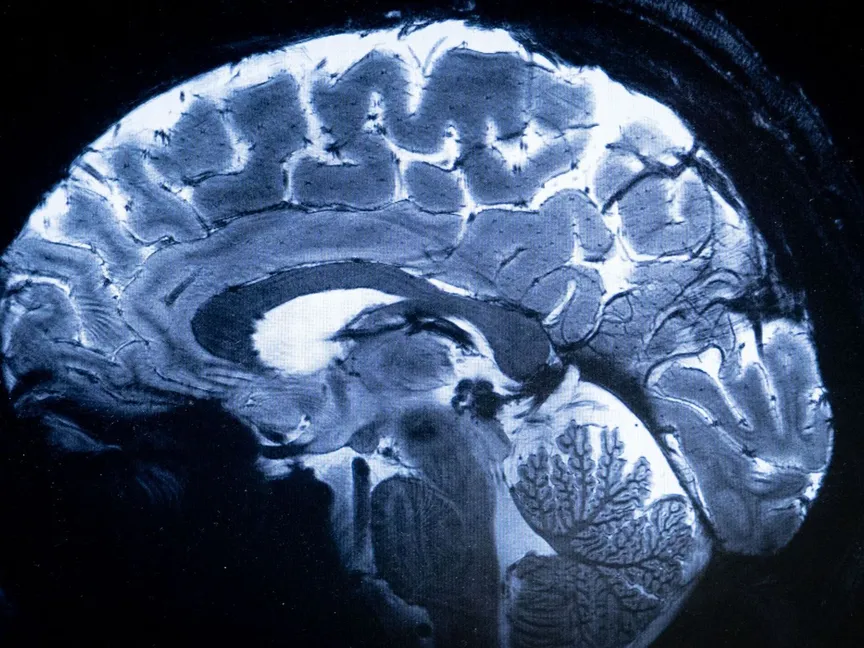

أثبتت تجربة بحثية أن الخلايا الدماغية البشرية قادرة على البقاء على قيد الحياة، خلال تواجدها في مدار الأرض المنخفض لأسابيع طويلة، وفق نتائج دراسة منشورة حديثاً، ما يفتح الباب أمام تطوير علاجات لأمراض مستعصية.

قاد فريق من الباحثين، بقيادة عالم الأحياء الجزيئية دافيدي ماروتا من مختبر المحطة الفضائية الدولية الوطني، دراسة لاستكشاف تأثيرات الجاذبية الدقيقة على الدماغ البشري، مع التركيز على الخلايا العصبية المتأثرة بالأمراض العصبية الانتكاسية مثل التصلب المتعدد، ومرض باركنسون.